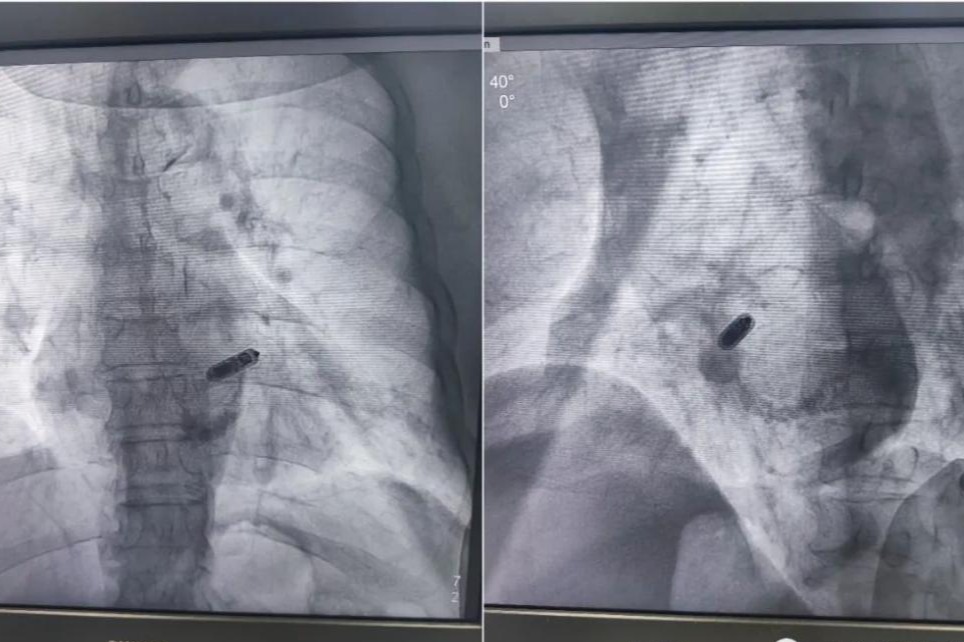

植入Micra后的心脏(分别是RAO和LAO体位)

术中进行股静脉穿刺,将Micra胶囊起搏器通过导管顺利植入到心脏内部—-右心室室间隔中部,手术全程仅用时30分钟。